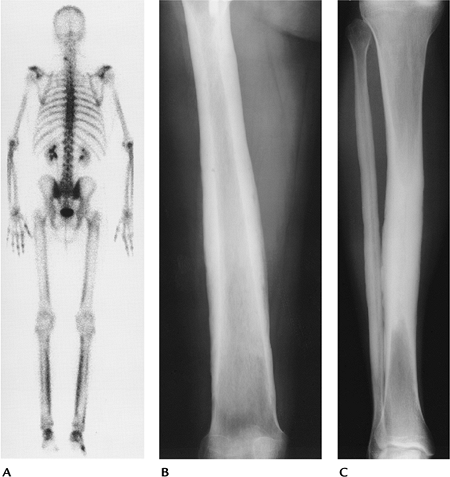

![]() |

FIGURE 15-6 Engelmann disease. (A)

Radionuclide bone scan showing symmetric increased cortical uptake in the femora, tibiae, and upper extremities. AP radiographs of the femur (B) and tibia (C) showing marked diaphyseal cortical thickening with sparing of the metaphyses and epiphyses. |